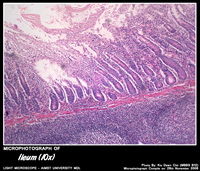

ILEUM

Histology of Ileum

• Has fewer villi,

• Very short broad tipped ( club shaped )

• Relatively abundant goblet cells.

• Lamina propria typically contains many lymphoid nodule clusters (Peyer’s patches).

• Bulge into luminal surface and extend into the luminal mucosa.